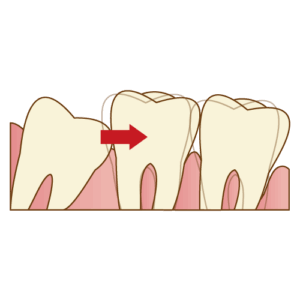

これが、私たちが最も避けたいケースです。 親知らずが斜めに生えていると、その手前にある**最も大切な「第二大臼歯(7番)」**の後ろ側に隙間ができ、食べカスが詰まりやすくなります。

結果として、親知らず自身だけでなく、健康だったはずの第二大臼歯が虫歯になったり、歯周病(歯を支える骨が溶ける病気)になってしまうのです。

親知らずは失っても噛み合わせに影響は出にくいですが、第二大臼歯を失うと、噛む機能が著しく低下します。

親知らずを守るために、その手前の重要な歯を犠牲にするわけにはいきません。

3. 歯並び全体を悪化させる原因になる

横向きに埋まっている親知らずが、手前の歯をぐいぐいと押し続けることで、前歯の歯並びがガタガタになってしまうことがあります。 「昔は綺麗だったのに、大人になってから前歯が重なってきた」という方の中には、親知らずが原因となっているケースも少なくありません。